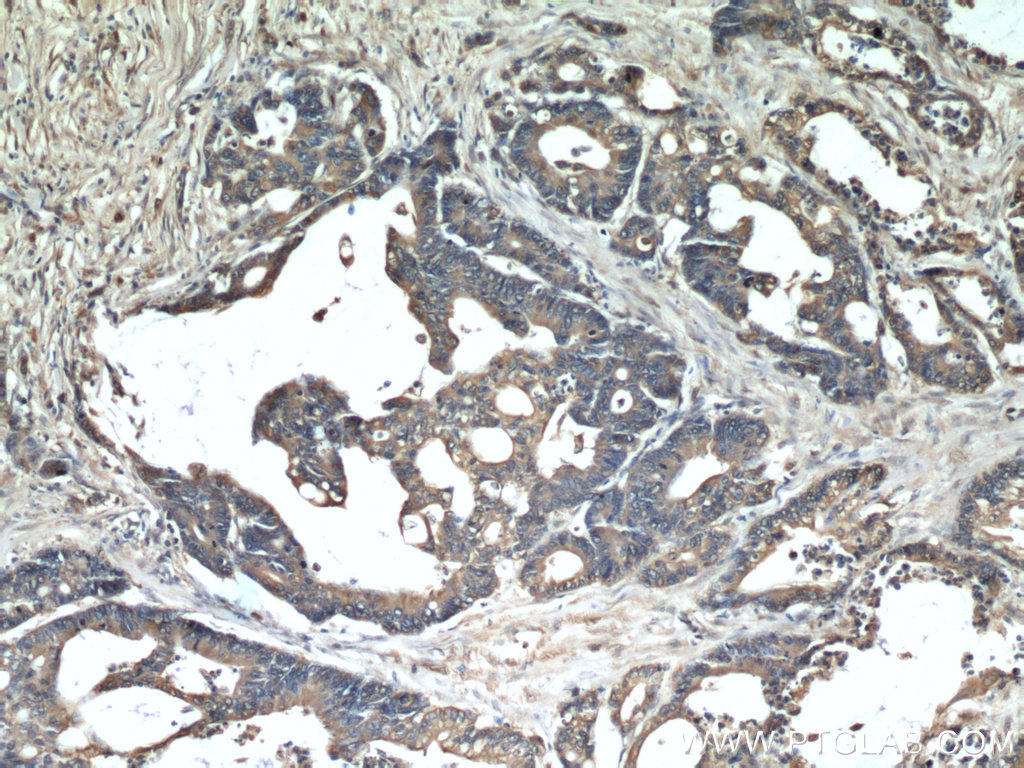

| Positive IHC detected in | human colon cancer tissue Note: suggested antigen retrieval with TE buffer pH 9.0; (*) Alternatively, antigen retrieval may be performed with citrate buffer pH 6.0 |

| Immunohistochemistry (IHC) | IHC : 1:100-1:1000 |